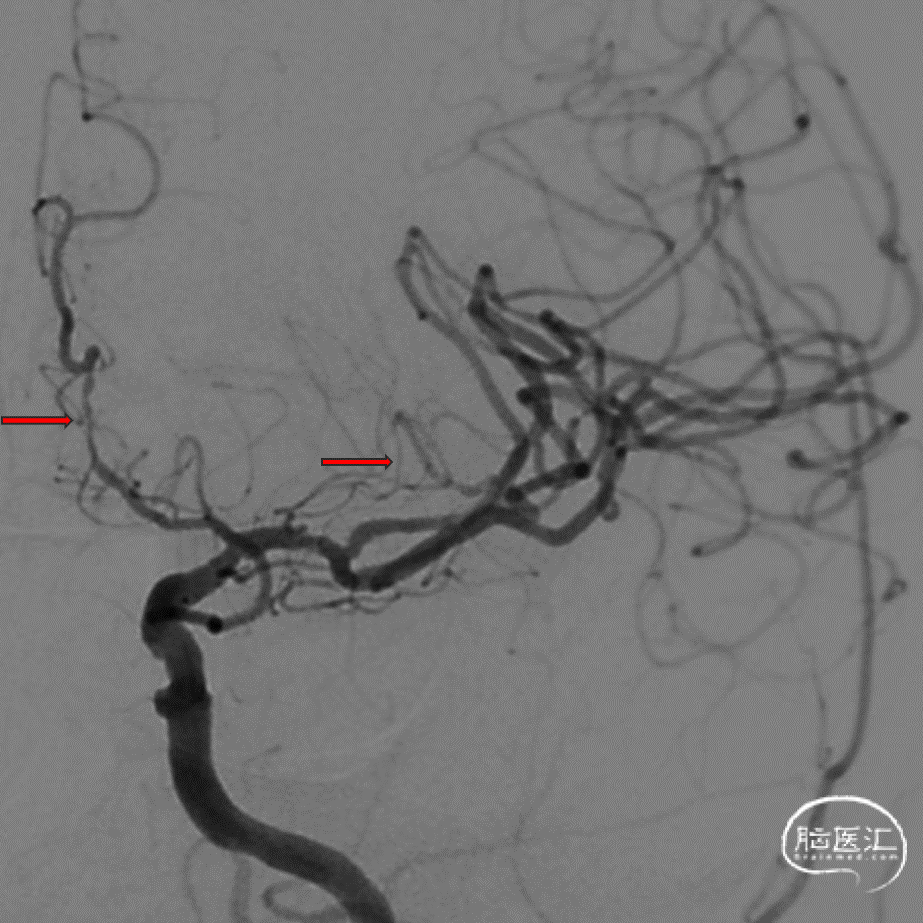

右侧大脑中动脉M1段次全闭塞,见一“搭桥”动脉形成,远端血管显影尚可;右侧椎动脉V3段走形迂曲,V4段重度狭窄(约95%)。

颅脑斑块分析:右侧大脑中动脉M1-3段混合斑块形成(易损斑块及少许血栓附着),管腔重度狭窄。

右颈造影:右侧颈内动脉走形迂曲,右侧大脑前动脉走形严重迂曲,管腔光滑,未见明显血管狭窄斑块。右侧大脑中动脉M1段次全闭塞,右侧大脑前动脉通过软脑膜动脉向右侧大脑中动脉供血区代偿供血,右侧颈外动脉通过颞浅动脉向右侧大脑中动脉供血区代偿供血,代偿2级。

2、DSA:右侧大脑中动脉M1段次全闭塞。